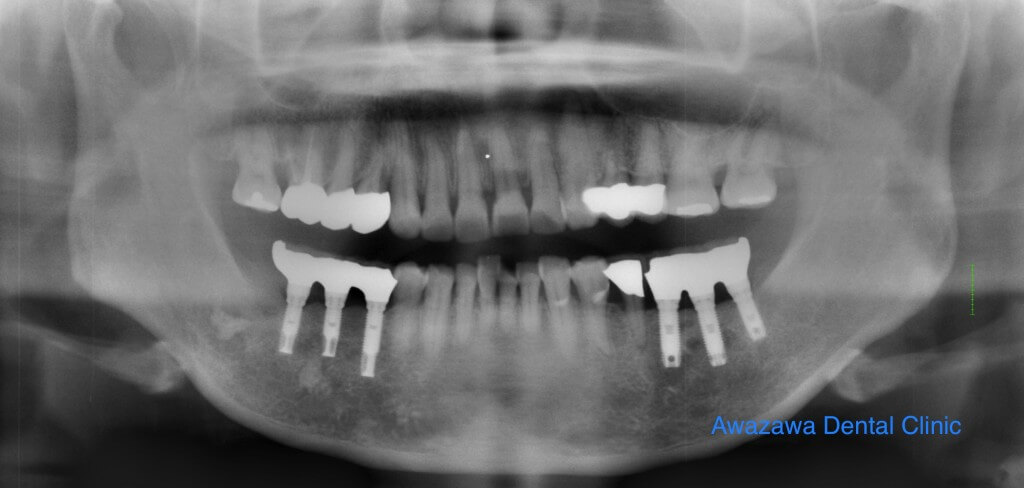

崩れてしまった奥歯のかみ合わせを修復した症例です。保存不可能な右下の奥歯は抜歯後インプラントにより補綴し、審美的な修復を行いました。(治療後の写真は治療終了1年経過後の状態です)